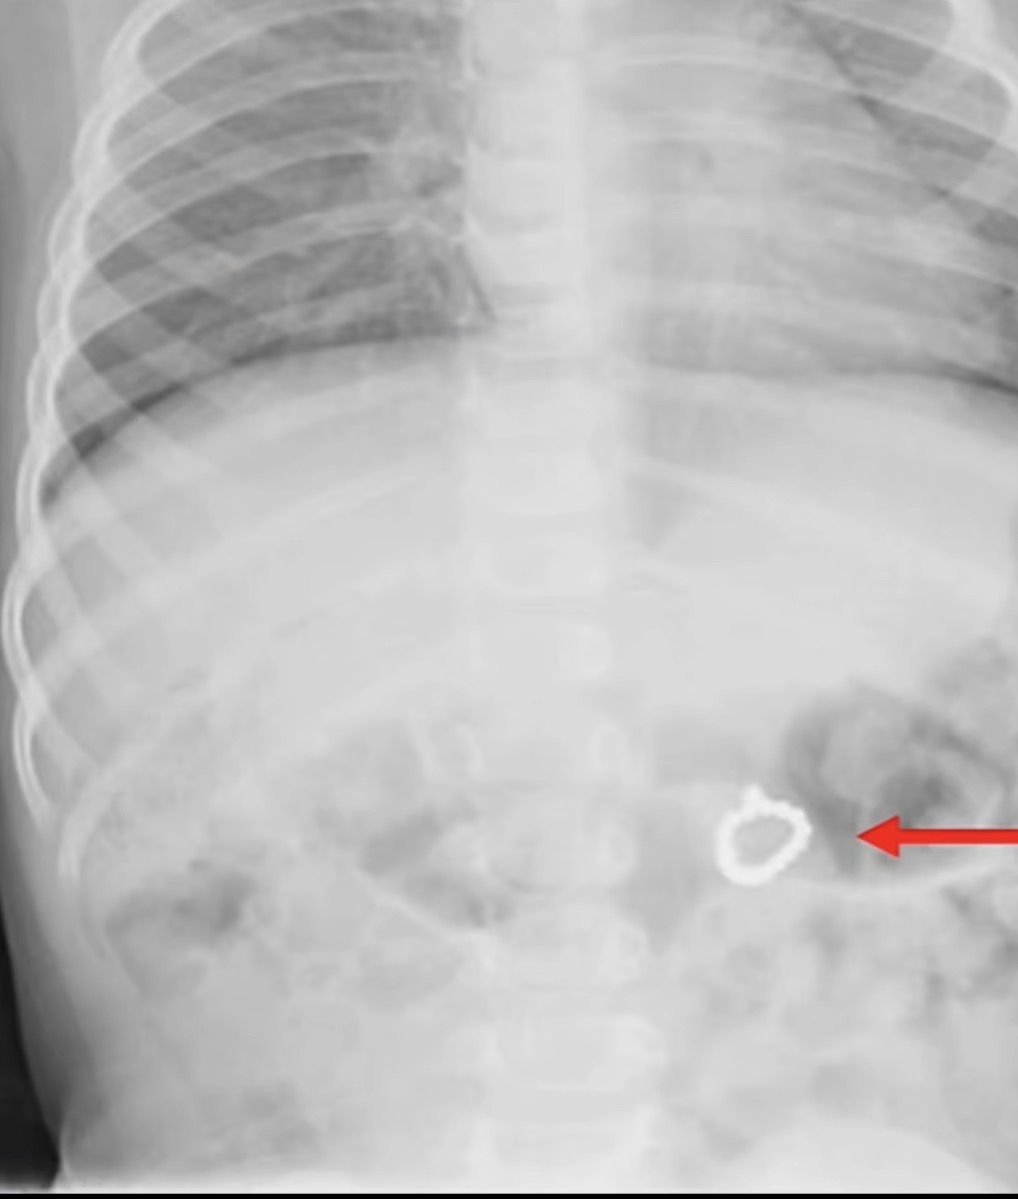

Pas ekzaminimeve, mjekët konstatuan se unaza ndodhej në stomakun e saj, duke shkaktuar panik, por fatmirësisht pa pasoja serioze për shëndetin.